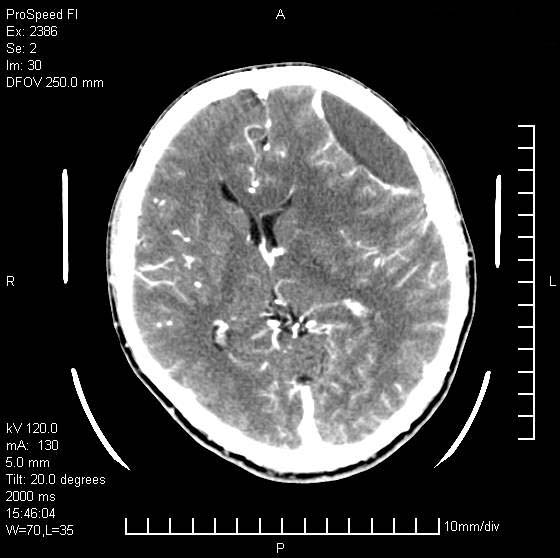

以下是引用天南地北在2007-9-19 18:43:00的发言:[br]典型慢性硬膜外血肿[br][br][本贴已被 天南地北 于 2007-9-19 18:44:11 修改过]

以下是引用曼一拍在2007-9-20 11:06:00的发言:[br]支持慢性硬膜下血肿.[br]慢性硬膜下积液:血肿有包膜,ct值稍高于脑脊液,增强可有染色。不典型者血肿可多呈梭形.是硬脑膜与蛛网膜之间的潜在腔隙内的血肿。[br]鉴别:[br]1\\硬膜外血肿:是颅脑外伤后脑膜或板障内血管破裂,血液在颅骨与硬膜之间积聚所致.通常是脑膜动脉破裂,也可因静脉窦破裂或颅骨的板障静脉出血,发生于外伤的着力部,常与颅骨骨折并存。脑膜动脉出血则急,若是板障静脉出血在则可有慢性。[br]2\\硬膜下积液:(硬膜下水瘤)[br]是由于蛛网膜破裂,脑脊液经蛛网膜破口进入硬膜下腔不能回流。或水肿阻塞而形成。[br]ct表现:颅骨内板下方新月形低密度区近似脑脊液密度;占位效应清,周围无脑水肿。[br]